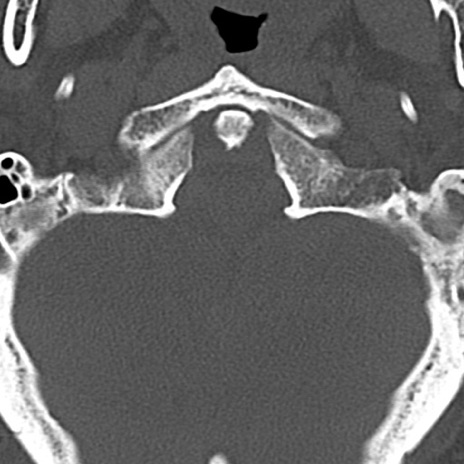

頚椎CT

冠状断像